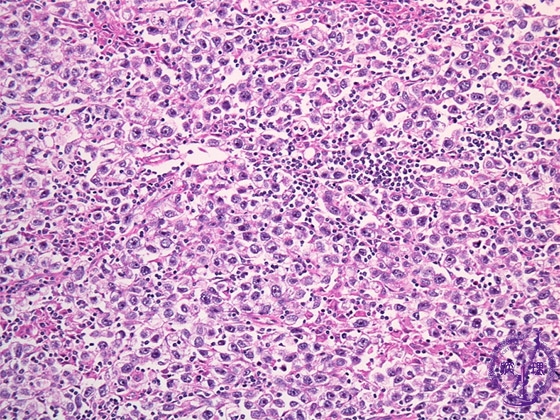

Histology (HE stain, intermediate power): Seminoma. Large rounded tumor cells have clear cytoplasm and glycogen in their cytoplasm.